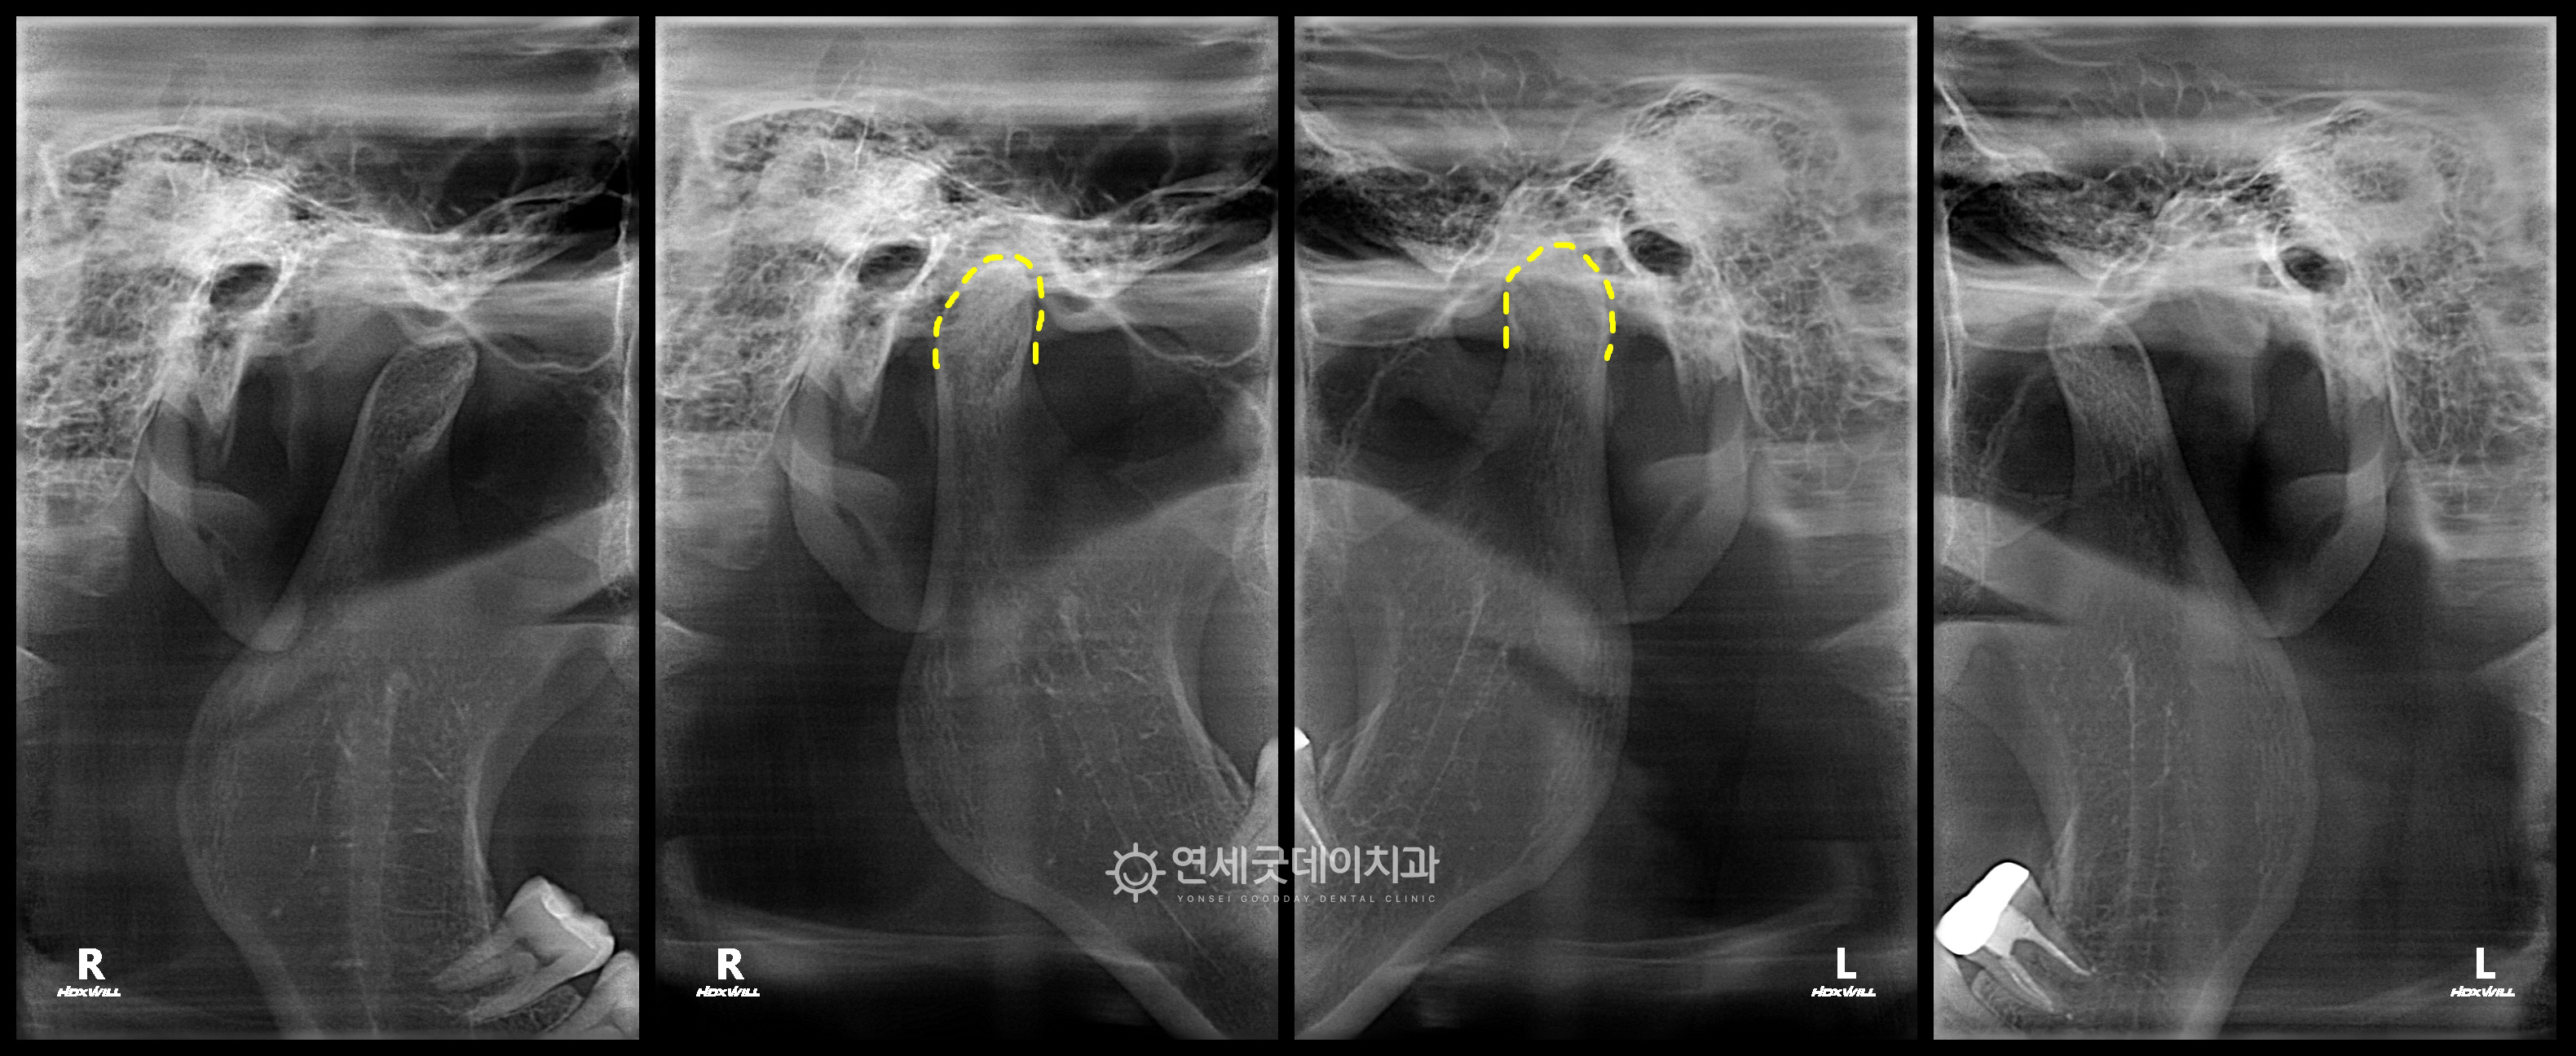

턱교정, 트랙션을 이용한 오픈바이트 치료전후

턱관절 파노라마를 촬영하였으며 다행히 현재 턱관절 관절염이 진행 중인 상태는 아니었으며 정밀진단 후 환자분께 3가지 치료 옵션을 설명드렸습니다. ➊ 트랙션 3번은 적극적인 치료 없이 경과를 관찰하는 방법이지만 환자분께서는 1번 트랙션 치료를 선택하셨으며

턱관절 파노라마 상에서도 턱관절은 아래턱과 혀의 위치 조절, 어깨 및 자세 교정 등